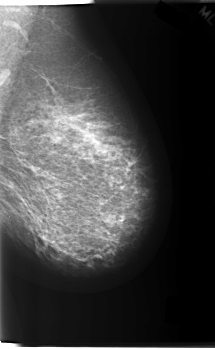

C_0213_1.LEFT_CC

LEFT_CC LINES 6016 PIXELS_PER_LINE 3384 BITS_PER_PIXEL 12 RESOLUTION 50 NON_OVERLAY